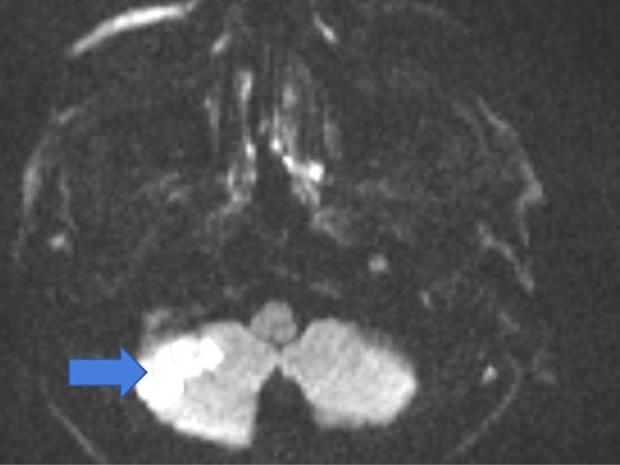

ففي الوقت الذي تعتقد فيه السيدات أن زيارة صالون التجميل الأهم في يومها، تصاعدت التحذيرات من احتمالية الإصابة بمتلازمة السكتة الدماغية في صالونات التجميل (BPSS)، وهي حالة نادرة، عُرفت لأول مرة عام 1993 من قبل الدكتور مايكل وينتراوب، الذي لاحظ وجود علاقة غريبة بين غسل الشعر في صالونات التجميل وأعراض السكتة الدماغية.

وأوضح الدكتور مايكل وينتراوب، إن السكتة الدماغية تحدث عندما ينقطع تدفق الدم إلى الدماغ، غالبًا بسبب جلطة أو تمزق الأوعية الدموية، فعندما يؤثر وضع الرقبة أثناء غسل الشعر في الصالون على تدفق الدم، قد يؤدي إلى مضاعفات خطيرة.

وضعية الرقبة السبب الحقيقي للأزمة، فعندما تتكئين على حوض المغسلة، تكون رقبتك ممدودة وأحيانا تهتز أثناء غسل الشعر، ووفقًا لصاحب الدراسة، يمكن أن يتسبب ذلك في ضغط أو تلف الأوعية الدموية المؤدية إلى الدماغ، أو حدوث بعض الأعراض مثل نتوءات العظام أو إصابات الرقبة أو مشكلات الأوعية الدموية، وقد يؤدي هذا الوضع إلى حدوث سكتة دماغية.